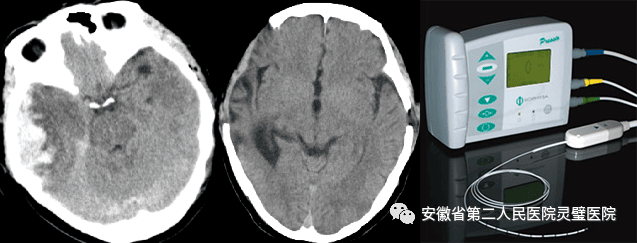

四、脑出血的综合治疗技术

脑出血是临床常见神经重症,原发性高血压是最常见原因之一,根据病人的不同特点,我科形成了从保守治疗、微创治疗到去大骨瓣减压等系列个性化特色技术,临床救治水平达到国内先进水平。

经额穿刺血肿引流术

经颞小骨窗神经内镜下血肿清除术

去大骨瓣减压术+脑内血肿清除术

六、DBS(脑深部电刺激)技术

DBS手术,又称脑起搏器,是治疗脑神经系统疾病的有效方法,它是在脑内特定的神经核团植入电极,释放高频电刺激,抑制过度兴奋的神经元的电冲动,减低了其过度兴奋的状态,从而减轻特发性震颤的症状,从而起到治疗的效果。